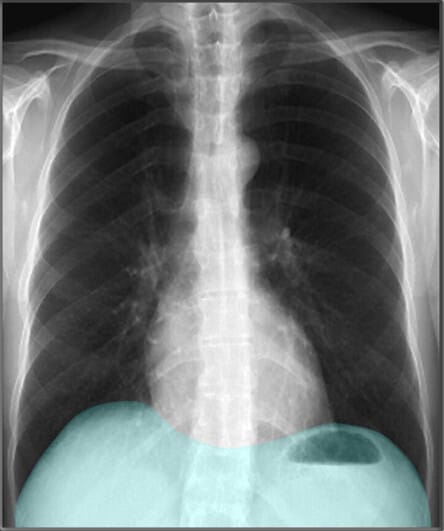

Chest PA view

PA (Posterior-anterior) – 방사선 (X선) 이 후방에서 전방으로 이동